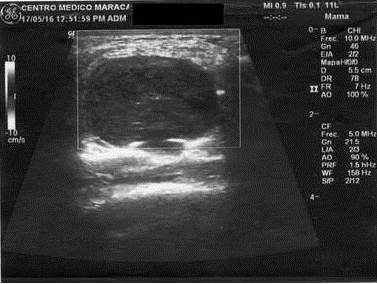

Paciente femenina de 30 años de edad presenta una masa tumoral en mama derecha de crecimiento rápido de 3 meses de evolución, no tiene antecedentes de enfermedad de neurofibromatosis en el grupo familiar ni ella lo presenta. Al examen físico se encuentra una masa tumoral de 16 cm. En diámetro mayor, firme no adherida a la piel ubicada en unión de cuadrantes externos (Figura 1). La paciente venía con una mamografía (Figura 2) y una ecografía mamaria (Figura 3)